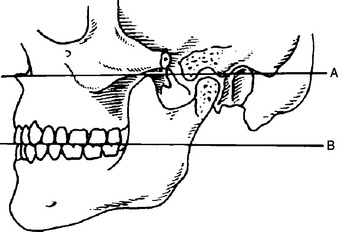

The angle between this line and the horizontal plane is 3on the panorex and 4on the. Focal trough layer that area between the x ray source and the image receptor that will be imaged distinctly on the panoramic. In other words the ala of the nose should be slightly inferior to the height of the tragus. These zones are as follows.

Important in determining the correct position of the patient s head. Exposure was 80 to 90 kv at 10 ma for 1 5 to 2 seconds in accordance with the subject s physical. The panorex i s. To achieve the correct vertical angulation the head must be positioned upright and symmetrical with the ala of the nose just inferior to the height of the tragus.

The cone film distance used was 5 feet. If the tragus is positioned above the tragus the hard palate will appear as a thick opaque horizontal opacity above over the apices of the maxillary anterior teeth and premolars. Download pdf 1mb sizes 0 downloads 9 views.